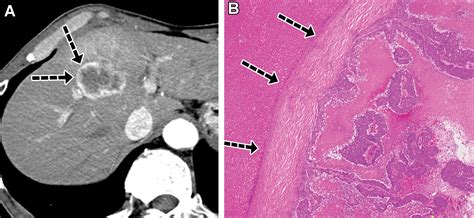

Abdominal CT Scan Provides detailed cross-sectional images to identify lesion size and location.

MRI with Contrast Highly sensitive; often used to differentiate benign lesions from metastases.

Liver Biopsy Definitive tissue analysis to determine the primary origin if unknown.